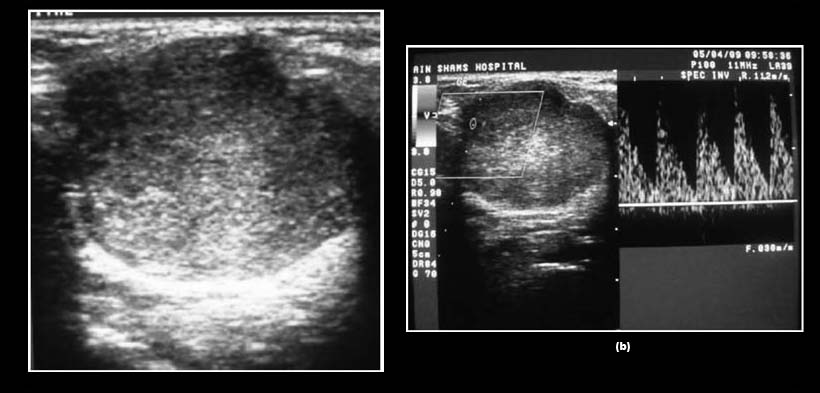

Fig. 2. (a) Ecografía en escala de grises (GSS) de una glándula parótida derecha ampliada que muestra una lesión hipoecoica bien definida, heterogénea, con múltiples áreas anecoicas y un componente sólido. (b) la ecografía Doppler a color (CDS) del mismo caso que muestra un Grado 3 vascularización dispersos, la ecografía Doppler espectral (SPD) muestra la velocidad sistólica máxima de 10,9 cm s21 (por debajo del nivel de umbral), de alto índice de resistencia de 0,89 (por encima del umbral nivel. El examen histopatológico reveló el diagnostico de carcinoma mucoepidermoide de la glándula parótida.